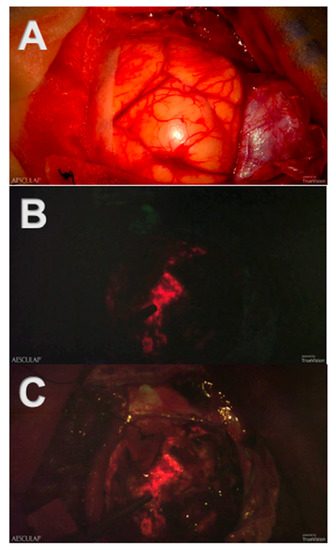

First, the visualization of tumor tissue and its discernment from healthy tissue is of utmost importance during neurooncological procedures. The introduction of 5-ALA-induced fluorescence has been a major scientific achievement in the intraoperative visualization of malignant tissue, which is independent of brain shift [14,15,16,17,18,19,20,21]. In conventional microscopic surgery, tumor tissue “glows” after preoperatively administered 5-ALA and intraoperative switching from conventional white light to a blue light source, which is integrated into the microscope. However, due to the dimming of white light, healthy, non-fluorescent brain tissue is barely visible in conventional microscopy, as illustrated in Figure 3.

The Three-Dimensional Robotic Digital Microscope combines the utilization of blue light and white light during the resection of high-grade malignant tumors using 5-ALA-induced fluorescence. Consequently, non-fluorescent brain tissue appears more visible next to fluorescent tumor tissue, and tumor’s margins become even more definable.

Figure 3. Screenshots of intraoperative recordings with Aeos during resection of a glioblastoma multiforme assisted by 5-ALA-induced PpIX fluorescence: (A) Conventional white light. The tumor and its margins are elusive under conventional white light. (B) Blue light. The tumor is clearly visible in strong fluorescence under dimmed white light and activated blue light. (C) Simultaneous usage of the white and blue light source: Tumor margins are easier to identify.